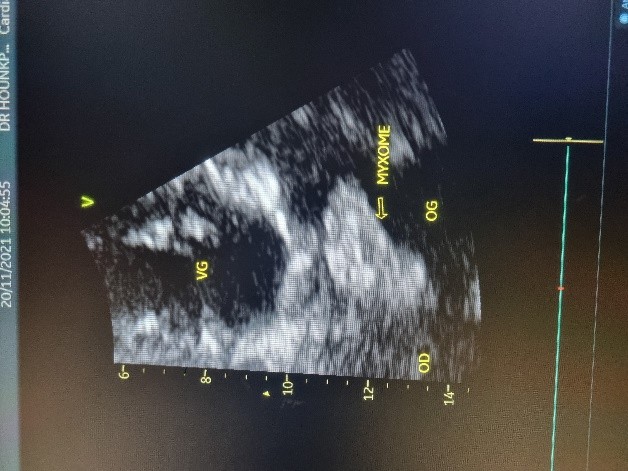

Figure 3 (a et b) : Echocardiographie transthoracique en mode bi dimensionnel montrant le myxome de l’oreillette gauche appendu au septum inter atrial vu en mode 4 cavités (a) et 2 cavités (b) chez un patient de 54 ans (Cas clinique n°2). VG= ventricule gauche; OG= oreillette gauche; OD= oreillette droite ; VD= ventricule droit.

(a)

(b)